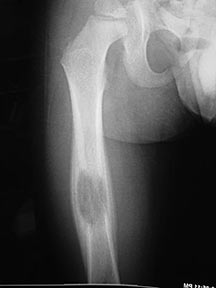

- May arise from any bone and any site within a bone (epiphyseal, metaphyseal, diaphyseal)

- Radiographically variable appearance: may appear benign (geographic) or malignant (permeative or moth eaten)

Sites:

- Femur